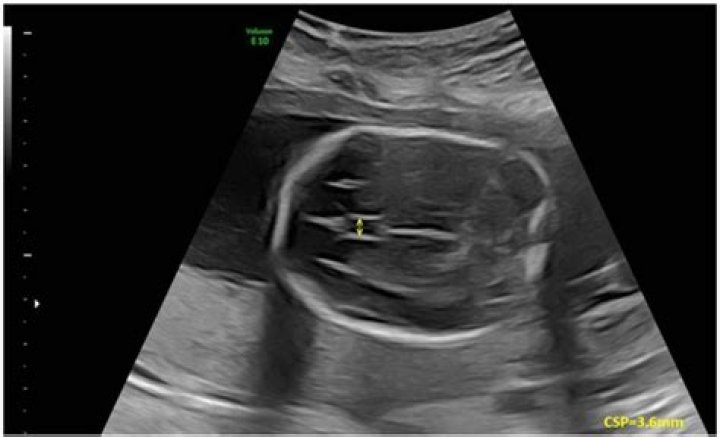

Cavum septi pellucidi (CSP) is an important landmark in the prenatal ultrasound evaluation of the fetal brain, and is a marker for normal central forebrain development. Examination of the fetal brain by MRI can confirm the sonographic findings and evaluate for associated anomalies.Click to see full answer. Considering this, what does the cavum septum pellucidum do?This is an important normal structure to identify in the sonographic assessment of the fetal brain. In post-natal life, the laminae of the septum pellucidum usually fuse, which obliterates the cavum. The cavity contains cerebrospinal fluid (CSF) that filters from the ventricles through the septal laminae.Additionally, what is absent cavum septum pellucidum? Absence of the Septum Pellucidum. The septum pellucidum (SP) is a thin membrane located at the midline of the brain. Children who are born without this membraine and also have other abnormalities–pituitary deficiencies and abnormal development of the optic disk–have a disorder known as septo-optic dysplasia. Also know, is cavum septum pellucidum dangerous? Symptomatic enlargement of the cavum septum pellucidum is rare and most commonly causes intermittent obstructive hydrocephalus with headache and loss of consciousness. It is amenable to surgical treatment such as cyst puncture or shunting, ventriculoperitoneal shunting, or radical excision.What fluid filled spaces does the septum pellucidum divide?The septum pellucidum (Latin for “translucent wall”) is a thin, triangular, vertical double membrane separating the anterior horns of the left and right lateral ventricles of the brain.